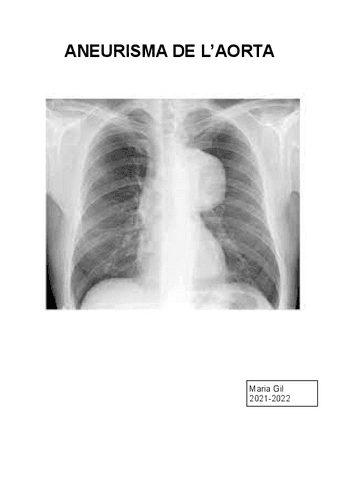

Trabajos - ANEURISMA-DE-LAORTA.pdf